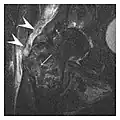

The greater tuberosity of the humerus is also an illustrative location of occult fractures. The osseous injury may follow seizures, glenohumeral dislocation, forced abduction, or direct impaction. They are commonly discovered on MRI in symptomatic patients with suspicion of rotator cuff tear. Coronal images are best suited for detection. They appear as crescentic oblique lines surrounded by a bone marrow edema pattern (Figure 5). The rotator cuff must be inspected since associated ligamentous lesions are common. In the ankle, malleoli and tarsal bones should be checked carefully for any cortical disruptions and radiolucent lines that may reveal a fracture. Awareness of the exact location of the pain will help direct the attention of the interpreter when searching for very subtle signs of fracture (Figure 6).[1]

a

b

Figure 6: Subtle anterior talar fracture in a 39-year-old man presenting with ankle pain after a fall. (a) Anteroposterior radiograph shows a subtle oblique radiolucent line through the talus (white arrows). (b) Sagittal CT reformation confirms the presence of an anterior talar fracture with cortical offset (black arrow). Avulsion fractures, which consist of a detached bone fragment resulting from a ligament or tendon pulling away from the bone, may also present with subtle radiographic signs. Tiny osseous fragments near the presumed attachment site of a ligament suggest this diagnosis. Common sites are the lateral tibial plateau (the Segond fracture), the spinal tuberosity of the tibia resulting from anterior cruciate ligament avulsion, and the ischial tuberosity.[1]